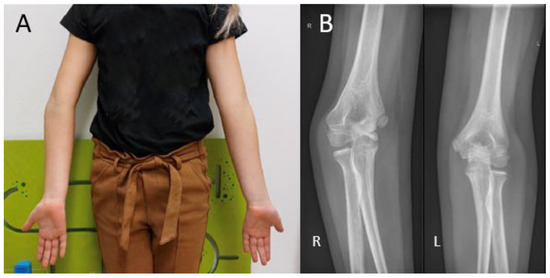

During visual inspection, the patient is placed in front of the examiner, standing in the anatomical position with both elbows fully extended (Figure 1). The carrying angle is measured best in a standing patient with arms in the anatomical position, with arms fully extended and wrists fully supinated. The carrying angle is the angle deviated from the line parallel to the humerus and the forearm. The carrying angle is usually greater in women, with an average of 15–20 degrees. In men, the carrying angle is, on average, 10–15 degrees [5,6,7]. Therefore, the carrying angle is compared best with the contralateral side. A physiological change in the carrying angle from valgus to varus can be observed as the patient flexes the elbow and supinates the forearm [8]. Assessment of the carrying angle is therefore performed in the same amount of flexion and rotation of both arms to optimize adequate comparison. In most female patients and children, a slight hyperextension of the elbow of 0 to 10 degrees is physiological [9]. Deformities in the sagittal plane are measured with the humerus in 90 degrees anteflexion and by flexing and extending the elbow with the forearm in a supinated position.

Cubitus varus is most often seen as late sequela after a distal humerus fracture (Figure 1B). The current stance in the literature is that it is caused by malunion of a humeral fracture rather than a growth arrest. The most common type of distal humerus fracture in children is the supracondylar fracture [25]. They are classified using the Gartland type classification, ranging from type I to type III, depending on the amount of posterior displacement of the capitellum and the intactness of the posterior humeral cortex [26]. Cubitus varus, however, results from displacement or comminution in the coronal plane. These injuries are often overlooked or difficult to judge on standard radiographs. Therefore, in type II and type III fractures, an oblique view may be helpful in identifying minimally displaced fractures [27]. Rotational malalignment can be difficult to assess radiographically. A high index of suspicion for rotational malalignment is required in cases of posteromedial displacement. These cases may also lead to a higher Baumann angle and hence combined cubitus varus deformity [28]. If missed or left untreated, the malunion leads to a progressive angular deformity in the coronal plane. The result at patient presentation is often a painless varus deformity evident at visual inspection that may not always be accompanied by limitations in ROM [25]. Although diagnosis is usually based on clinical evaluation alone, measuring the radiological Baumann angle compared to the contralateral side may give a more accurate measure of the extent of the deformity.

Figure 1. (A) Visual inspection of the carrying angle of the elbow in a 10-year-old girl showing a unilateral cubitus varus on the right side. (B) Anteroposterior radiographic views of the elbow with the unaffected contralateral side for comparison.